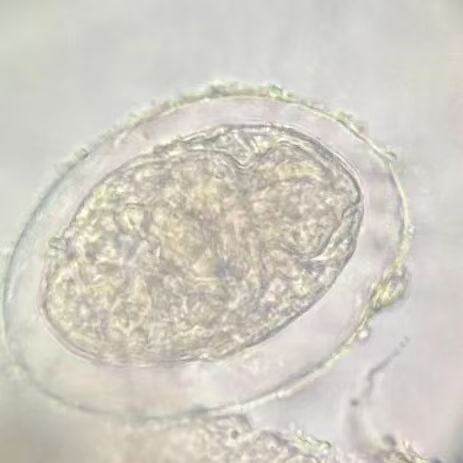

二等奖

第五组

郭 洁 楼姝含 吴佳慧 卢柯颖